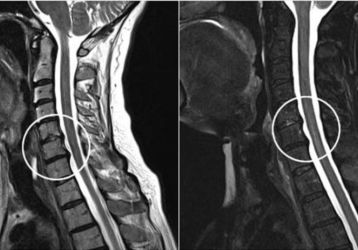

Причины, диагностика и лечение корешкового синдрома шейного отдела позвоночника

Признаки и симптомы корешкового синдрома в шейном отделе: описание, виды по локализации. Диагностика, методы лечения патологии, меры профилактики и прогноз.